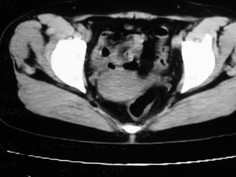

女42岁肛门下坠感4月余.

子宫轻度右倾,体后方见小似新月形低密度区,边界清楚。余所见无明显异常。

考虑:子宫直肠窝少量积液(盆腔炎所致)。

子宫轻度右倾,体后方见小似新月形低密度区,道格拉斯窝周围间隙欠清晰,有索条模糊影阴,多考虑:肛周脓肿可能性大。